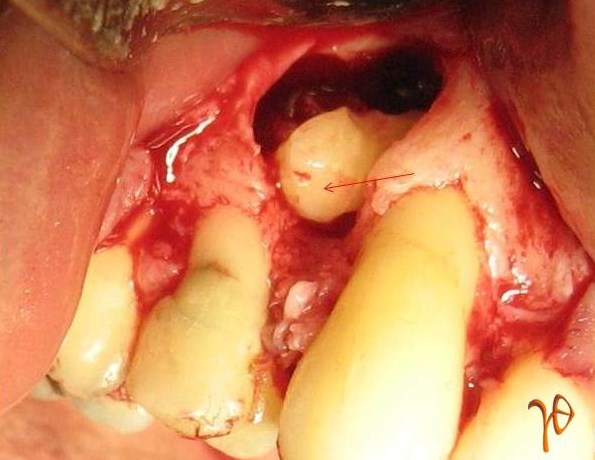

Οι πιο συχνές βλάβες από ερεθισμό στο στόμα είναι τα αντιδραστικά ινώματα (Εικόνες 4 και 5).

Εικόνα 4. α. Ίνωμα της υπερώας από χρόνιο ερεθισμό ολικής οδοντοστοιχίας (βέλος), β. Μετά την χειρουργική του αφαίρεση.